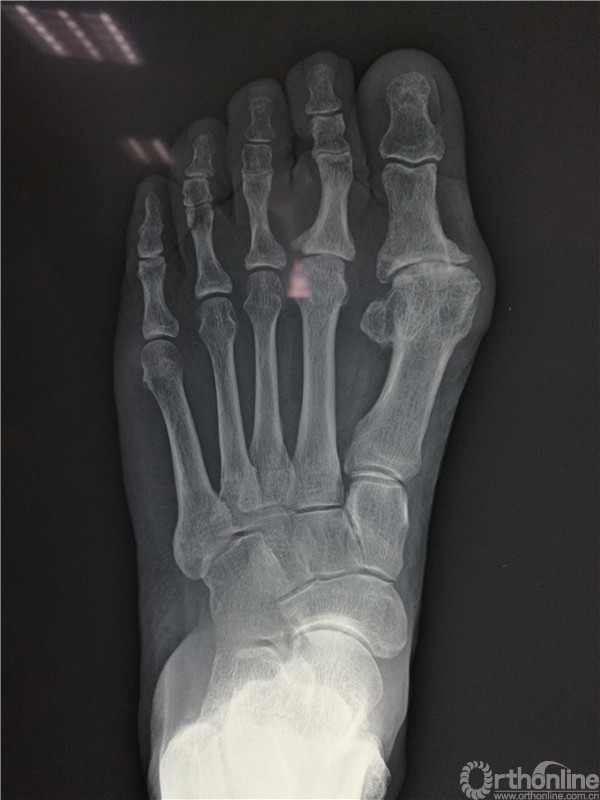

2016年4月7日,烟台市烟台山医院南院骨科收治一例左足跖趾关节骨性关节炎的病人,患者左足严重疼痛10余年,要求治疗的心情迫切。

在张树栋院长及刘克贵主任的支持下,南院骨科组织多次病例讨论,制定了一套对病人有效的治疗方案。以刘克贵主任,孙冰,李宏彦组成的医疗小组。于2016年4月9日上午九时,在腰麻下行左足第1、2 跖趾关节人工关节置换术,患者术后左足的疼痛明显减轻,功能良好,外形美观。